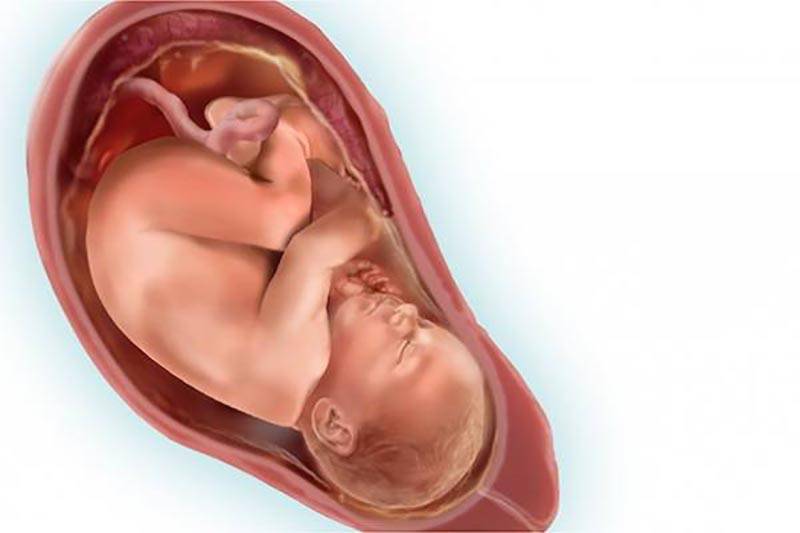

Фотография Плода В Животе

Фотография Плода В Животе 113 фотографий